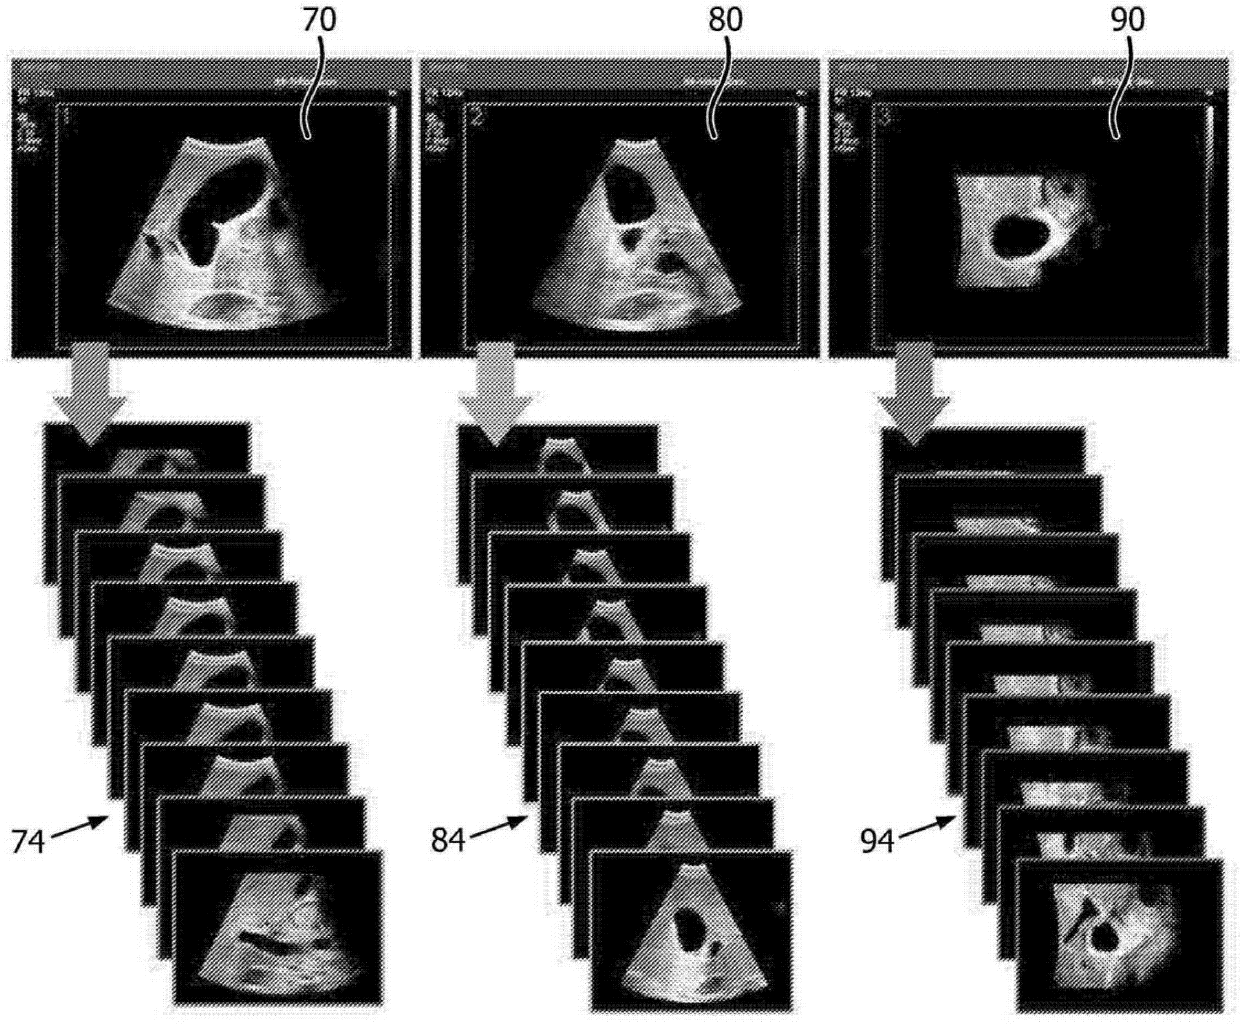

体积超声图像数据重新格式化为图像平面序列